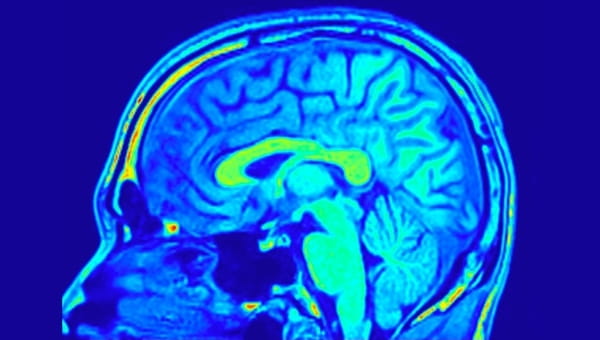

The Neurosciences Institute at Morton Plant Hospital in Clearwater, Florida combines the advanced medical specialties of neurology and neurosurgery to create a strong medical advantage in the treatment of brain, spinal cord, nervous disorders and stroke. As the first program of its kind in our community, The Neuroscience Institute leads the way in high-quality, neuroscience care.